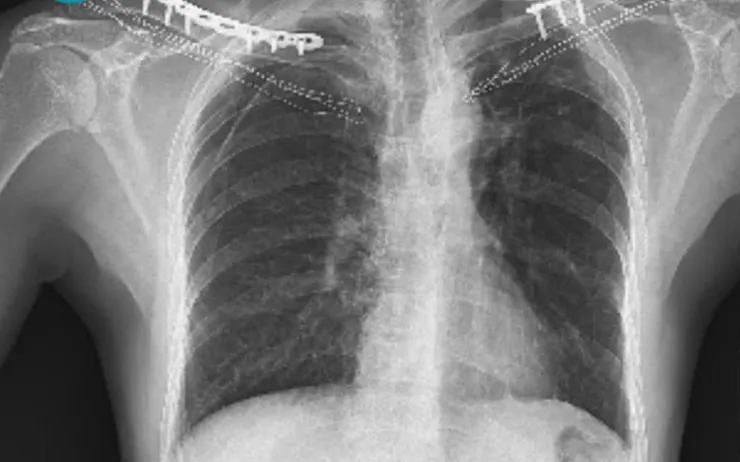

Bệnh nhân bị gãy xương đòn. Ảnh: BVCC

Tại Bệnh viện Đa khoa Hà Đông (Hà Nội), người bệnh được tiếp nhận trong tình trạng đau nhiều vùng vai - đòn hai bên, hạn chế vận động tay, sưng nề và bầm tím rõ. Kết quả chụp X-quang cho thấy gãy xương đòn hai bên - dạng chấn thương ít gặp dù cơ chế tai nạn giao thông khá phổ biến.

Sau khi thăm khám toàn diện, loại trừ các tổn thương phối hợp vùng ngực, cột sống cổ, mạch máu và thần kinh, các bác sĩ đã chỉ định phẫu thuật kết hợp xương bằng nẹp vít hai bên. Sau mổ, hai xương đòn được nắn chỉnh tốt, vết mổ ổn định, tạo điều kiện thuận lợi cho giảm đau và phục hồi chức năng sớm.